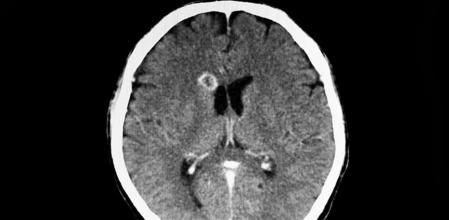

Las pruebas de imagen como la tomografía computerizada (TC), la resonancia magnética (RM) o las radiografías son las principales pruebas para detectar la presencia del parásito. También se puede realizar un análisis de sangre para detectar anticuerpos, un examen ocular de fondo de ojo o una punción lumbar para detectar la presencia o no en la columna vertebral.